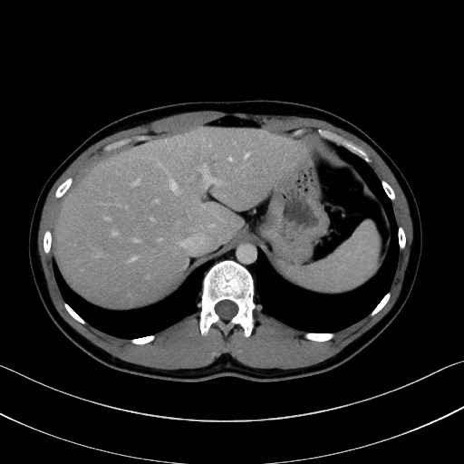

【症例】20歳代 男性 スクリーニング

脾動脈の画像解剖

■起始:典型的には腹腔動脈幹(celiac trunk)から左胃動脈・総肝動脈とともに三分岐し、脾動脈は左後上方へ向かう。

■走行:膵上縁または膵実質背側を蛇行しながら左方へ進み、膵尾部近傍で脾門へ至る。蛇行の程度は個体差が大きい。

■終枝:脾門部で複数の終末枝に分かれ、上極・下極枝や脾門枝群を形成する。胃短動脈群や左胃大網動脈はしばしば脾動脈から分岐する。